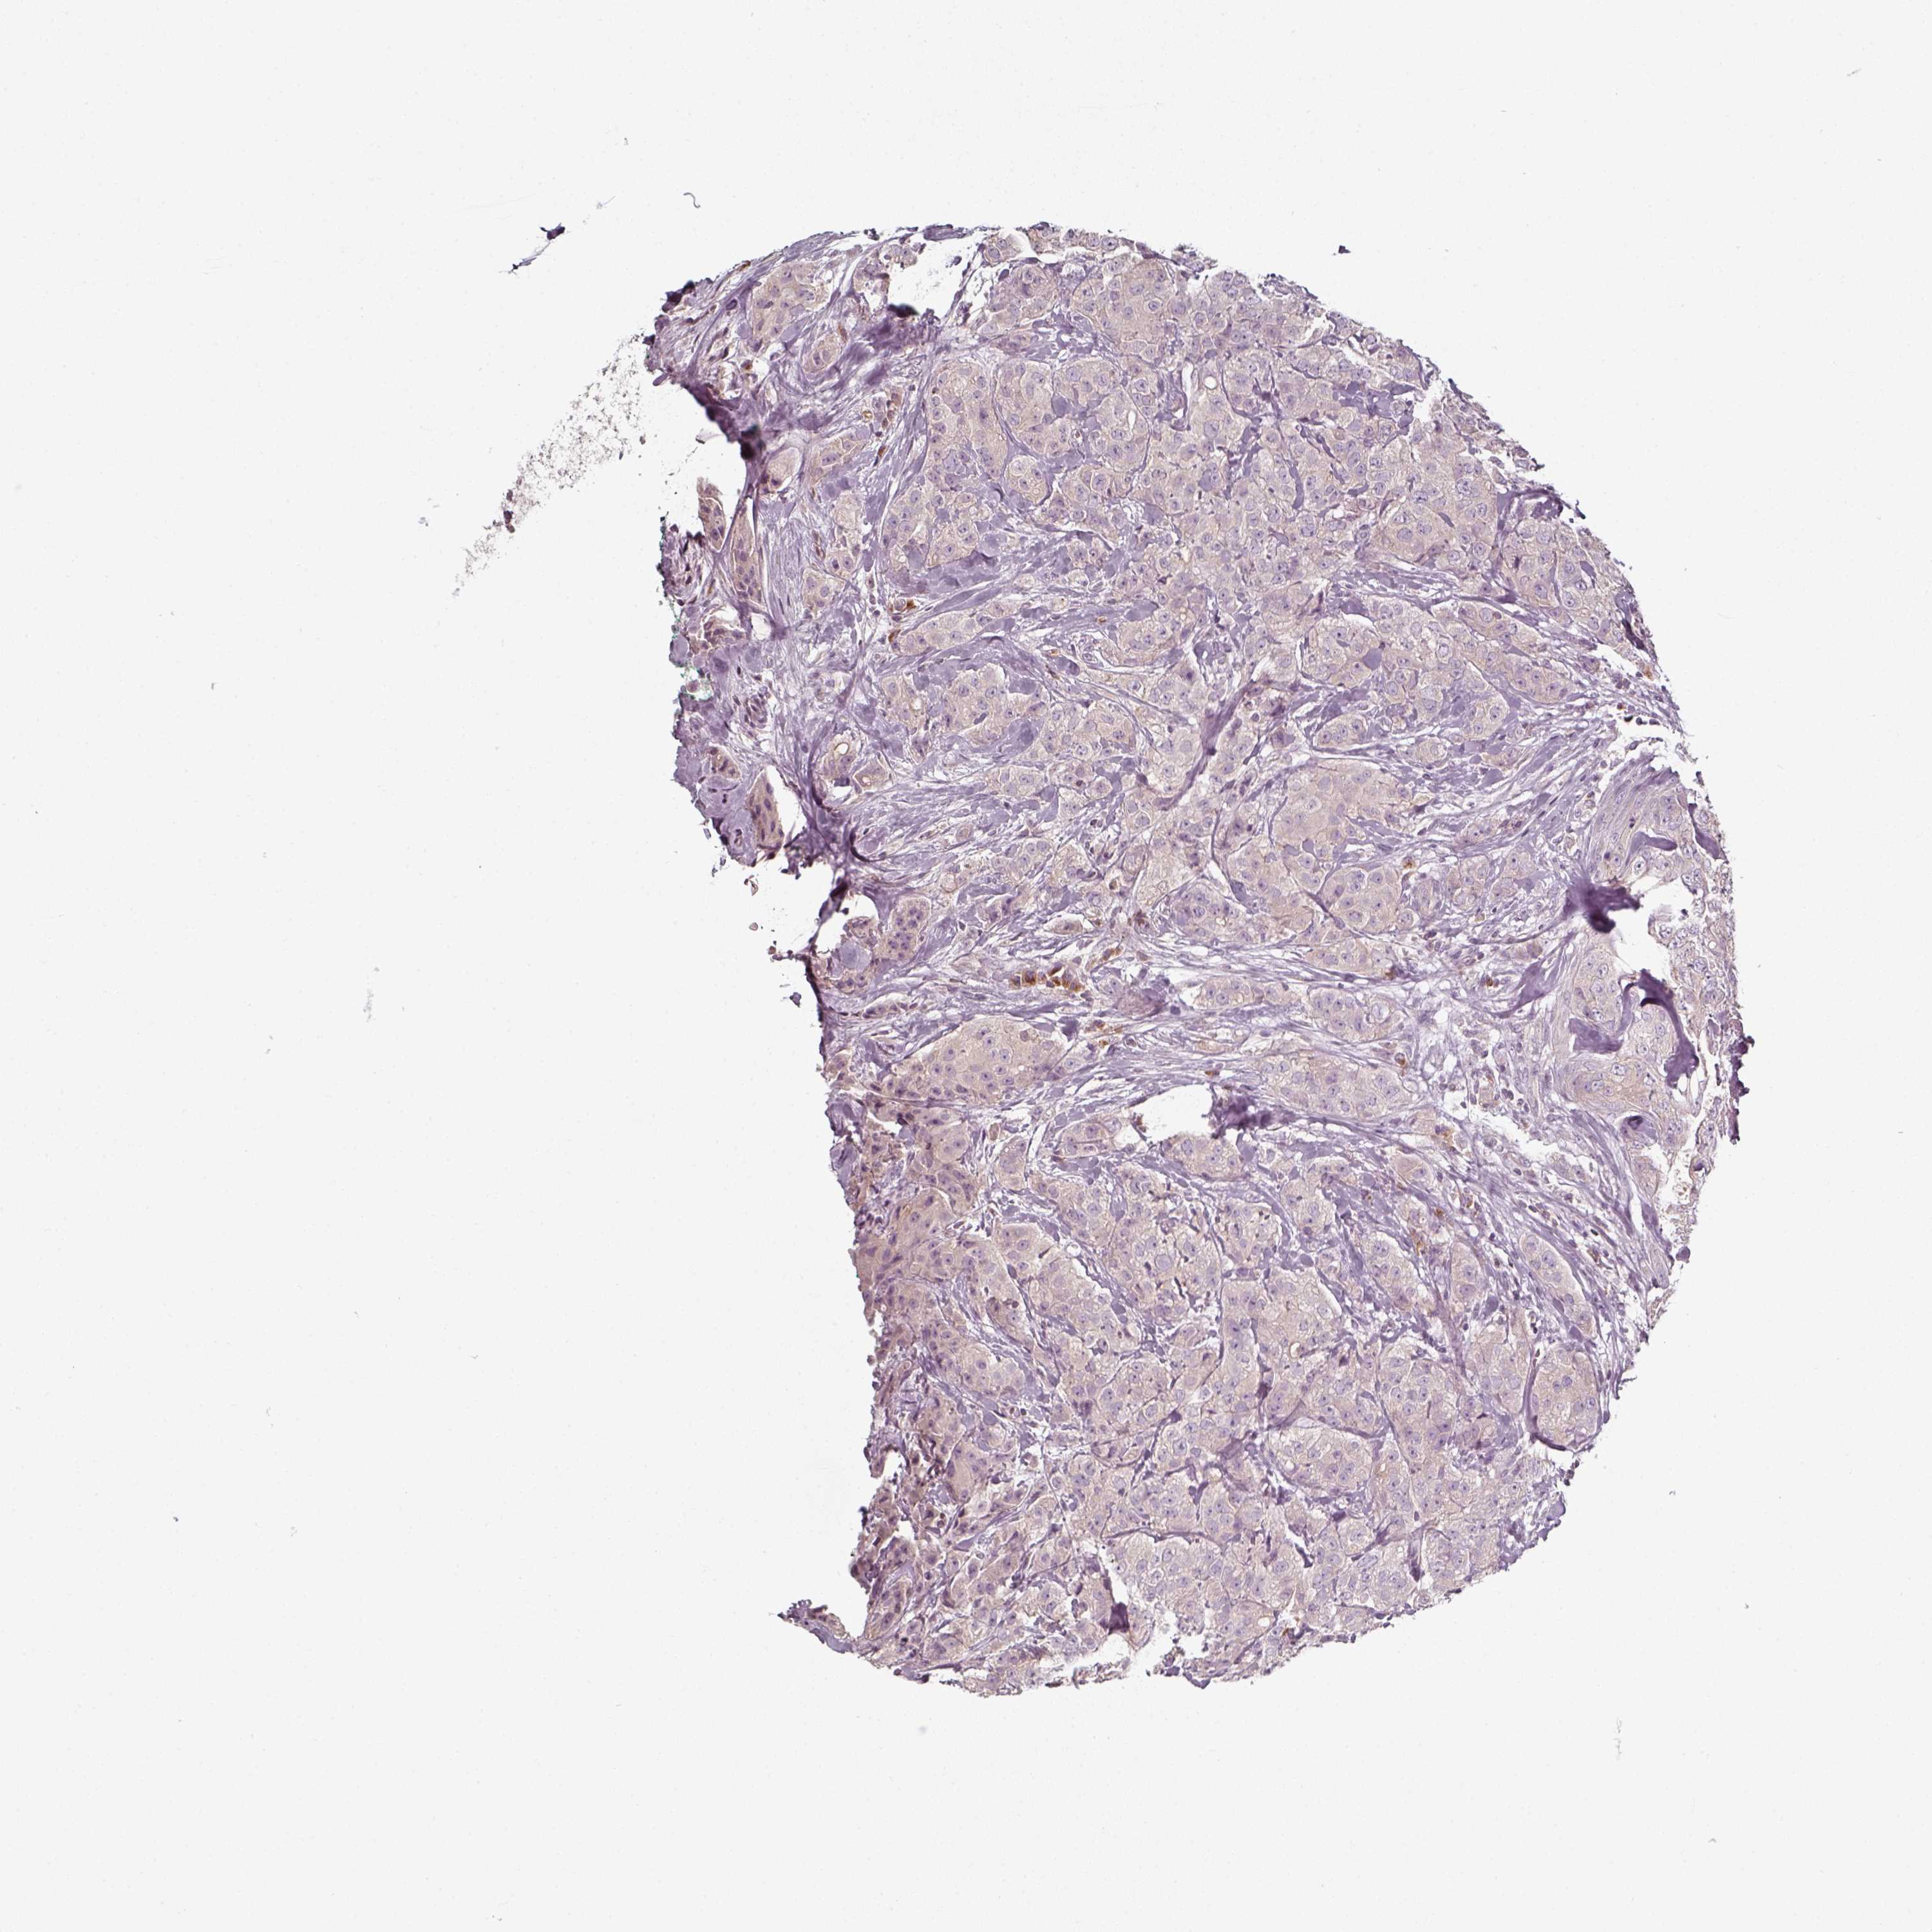

CANCER BREAST CANCER Show tissue menu

BRCA TCGA BRCA VALIDATION PROTEIN EXPRESSION